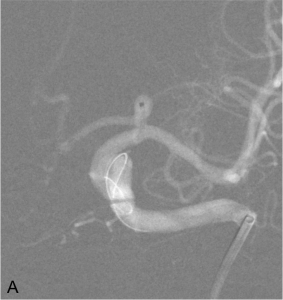

Exemple d’embolisation par coiling simple. A. Angiographie montrant l’anévrysme en position communicante

postérieure. B. Mise en place du microcathéter dans l’anévrysme. C. Résultat après le déploiement des coils ;

occlusion complète de l’anévrysme.